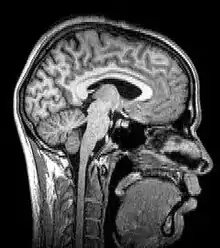

Imagen por resonancia magnética (MRI)

Las más modernas variaciones de la tomografía involucran la proyección de datos provenientes de múltiples direcciones y el envío de estos datos para la creación de una reconstrucción tomográfica a partir de un algoritmo de software procesado por ordenador. Los diferentes tipos de adquisición de las señales pueden ser utilizados en algoritmos de cálculo similares, a fin de crear una imagen tomográfica. Actualmente, las tomografías se obtienen utilizando diferentes fenómenos físicos, tales como rayos X, rayos gamma, aniquilación de electrones y positrones - reacción, resonancia magnética nuclear, Ultrasonido, iones y electrones. Estos se denominan: TC, SPECT, PET, MRI, ultrasonografía, 3D TEM y átomo sonda, respectivamente.